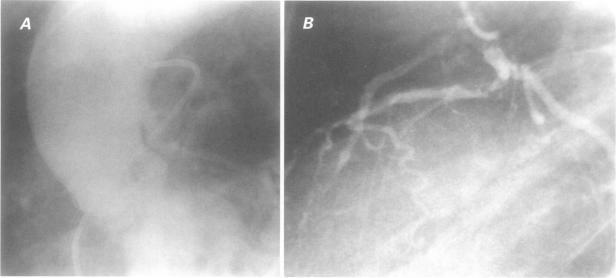

We reviewed the records of 10,661 patients who had undergone coronary angiography at the Clayton Foundation Cardiovascular Laboratories between 1 June 1974 and 15 March 1986, and identified major coronary artery anomalies in 83 adults. In addition, we included in our review 9 adults and 2 adolescents who had been referred for evaluation of anomalies documented elsewhere. Here we present the clinical and angiographic data for all 94 patients (76 men and 18 women). Most patients were men who presented with chest pain. The most common anomaly, found in 38 patients, was origin of left circumflex coronary artery from right coronary artery or right aortic sinus. In contrast to other studies, which have not shown increased incidence of coronary atherosclerosis in the anomalous circumflex artery, 71% of our patients with this anomaly had significant coronary atherosclerosis in the proximal portion of the anomalous vessel. The posterior course of the anomalous circumflex coronary artery may predispose this vessel to atherosclerosis in patients with coronary disease. The overall incidence of atherosclerotic disease in coronary arteries was 68% (64 of 94 patients) in the present study.

我们回顾了1974年6月1日至1986年3月15日期间在克莱顿基金会心血管实验室接受冠状动脉造影的10661例患者的记录,在83例成年人中发现了主要冠状动脉异常。此外,我们的回顾纳入了9例成年人和2例青少年,他们因其他地方记录的异常情况而被转诊进行评估。在此,我们展示了所有94例患者(76例男性和18例女性)的临床和血管造影数据。大多数患者为出现胸痛的男性。在38例患者中发现的最常见异常是左旋支冠状动脉起源于右冠状动脉或右主动脉窦。与其他未显示异常左旋支动脉中冠状动脉粥样硬化发病率增加的研究不同,我们患有这种异常的患者中有71%在异常血管近端有明显的冠状动脉粥样硬化。异常左旋支冠状动脉的走行可能使患有冠心病的患者该血管易患动脉粥样硬化。在本研究中,冠状动脉中动脉粥样硬化疾病的总体发病率为68%(94例患者中的64例)。